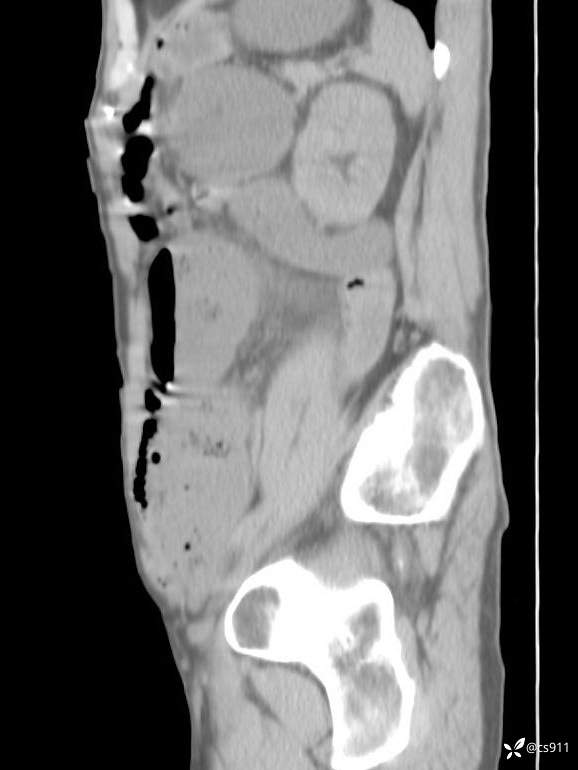

急腹症之急诊CT,原因?答案公布

男,77岁,腹痛、腹胀伴恶心呕吐1天。呕吐胃内容物,非喷射性呕吐,有咖啡色样胃内容物,诉有胃穿孔病史。查体:全腹平,下腹部压痛,全腹无反跳痛,叩诊呈浊音,移动性浊音阴性,肠鸣音减弱,1-2次/分。肛检:直肠未扪及明显肿物,可触及大量粪块。

T 36.6℃ P 80次/分 R 26次/分 BP 100/60mmHg

白细胞(WBC) H 14.55 10e9/L 4-10

红细胞(RBC) 4.58 10e12/L 4.3-5.8

中性粒细胞百分率(NEUT%) H 85.7 % 40-75

血淀粉酶(AMY) HH 1859 U/L 35-135

癌胚抗原(CEA) H 27.44 ng/ml 0-5

呕吐物 潜血试验 * 阳性 阴性

患者轮椅入室检查神志清楚, 能配合摆位和呼吸